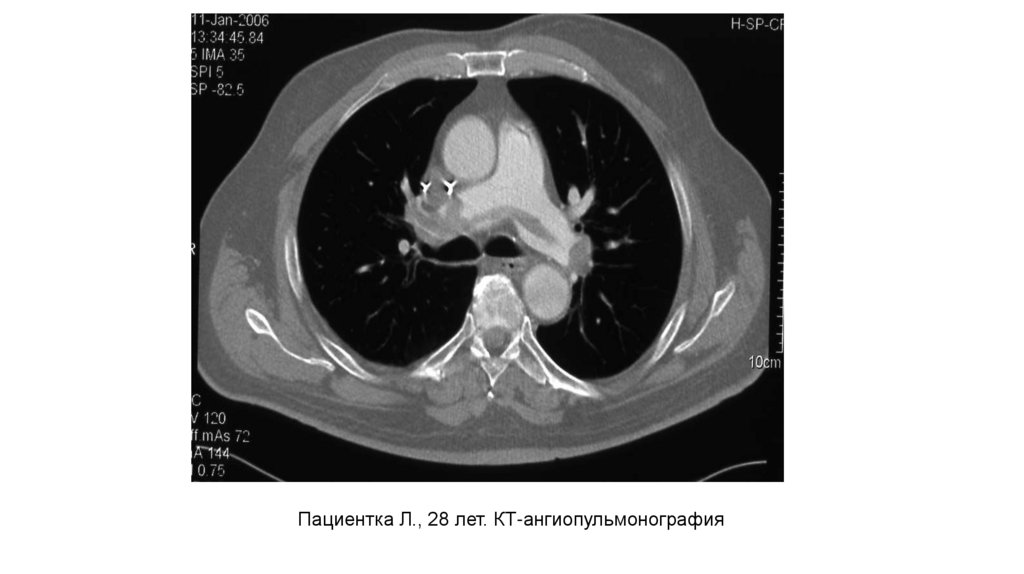

Пациентка Л., 28 лет. КТ-ангиопульмонография

4.